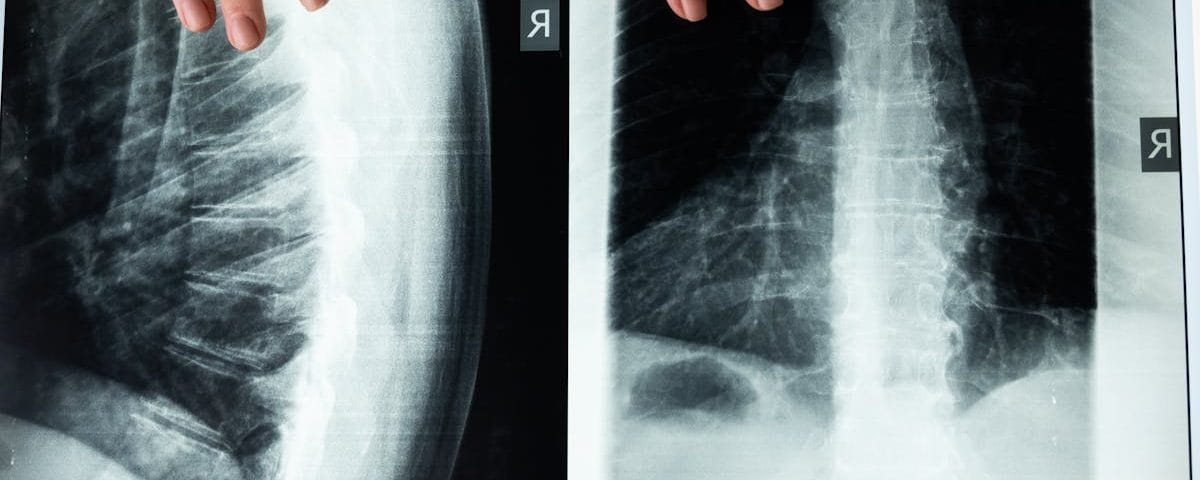

Expliquer le mécanisme de la décompression vertébrale

La décompression neurovertébrale agit en étirant doucement la colonne vertébrale, ce qui permet de créer un espace entre les vertèbres. Cette technique vise à réduire la pression sur les disques intervertébraux, ce qui est particulièrement bénéfique pour les personnes ayant des problèmes tels que les hernies discales, les bombements discaux ou d’autres pathologies vertébrales. En desserrant les tensions et en libérant les nerfs compressés, la décompression vertébrale aide à restaurer une fonction nerveuse optimale et à améliorer le flux sanguin dans la région de la colonne.

Lorsqu’elle est pratiquée de manière adéquate, la décompression neurovertébrale peut favoriser un soulagement significatif des douleurs chroniques, telles que celles causées par des hernies discales ou des sciatique. Grâce à des appareils de traction spécialement conçus, cette méthode agit en étirant progressivement la colonne vertébrale, permettant ainsi de créer un espace entre les vertèbres. Cela favorise non seulement la circulation sanguine mais également la régénération des tissus et la réduction de l’inflammation, tous des facteurs clés pour retrouver un état de bien-être.